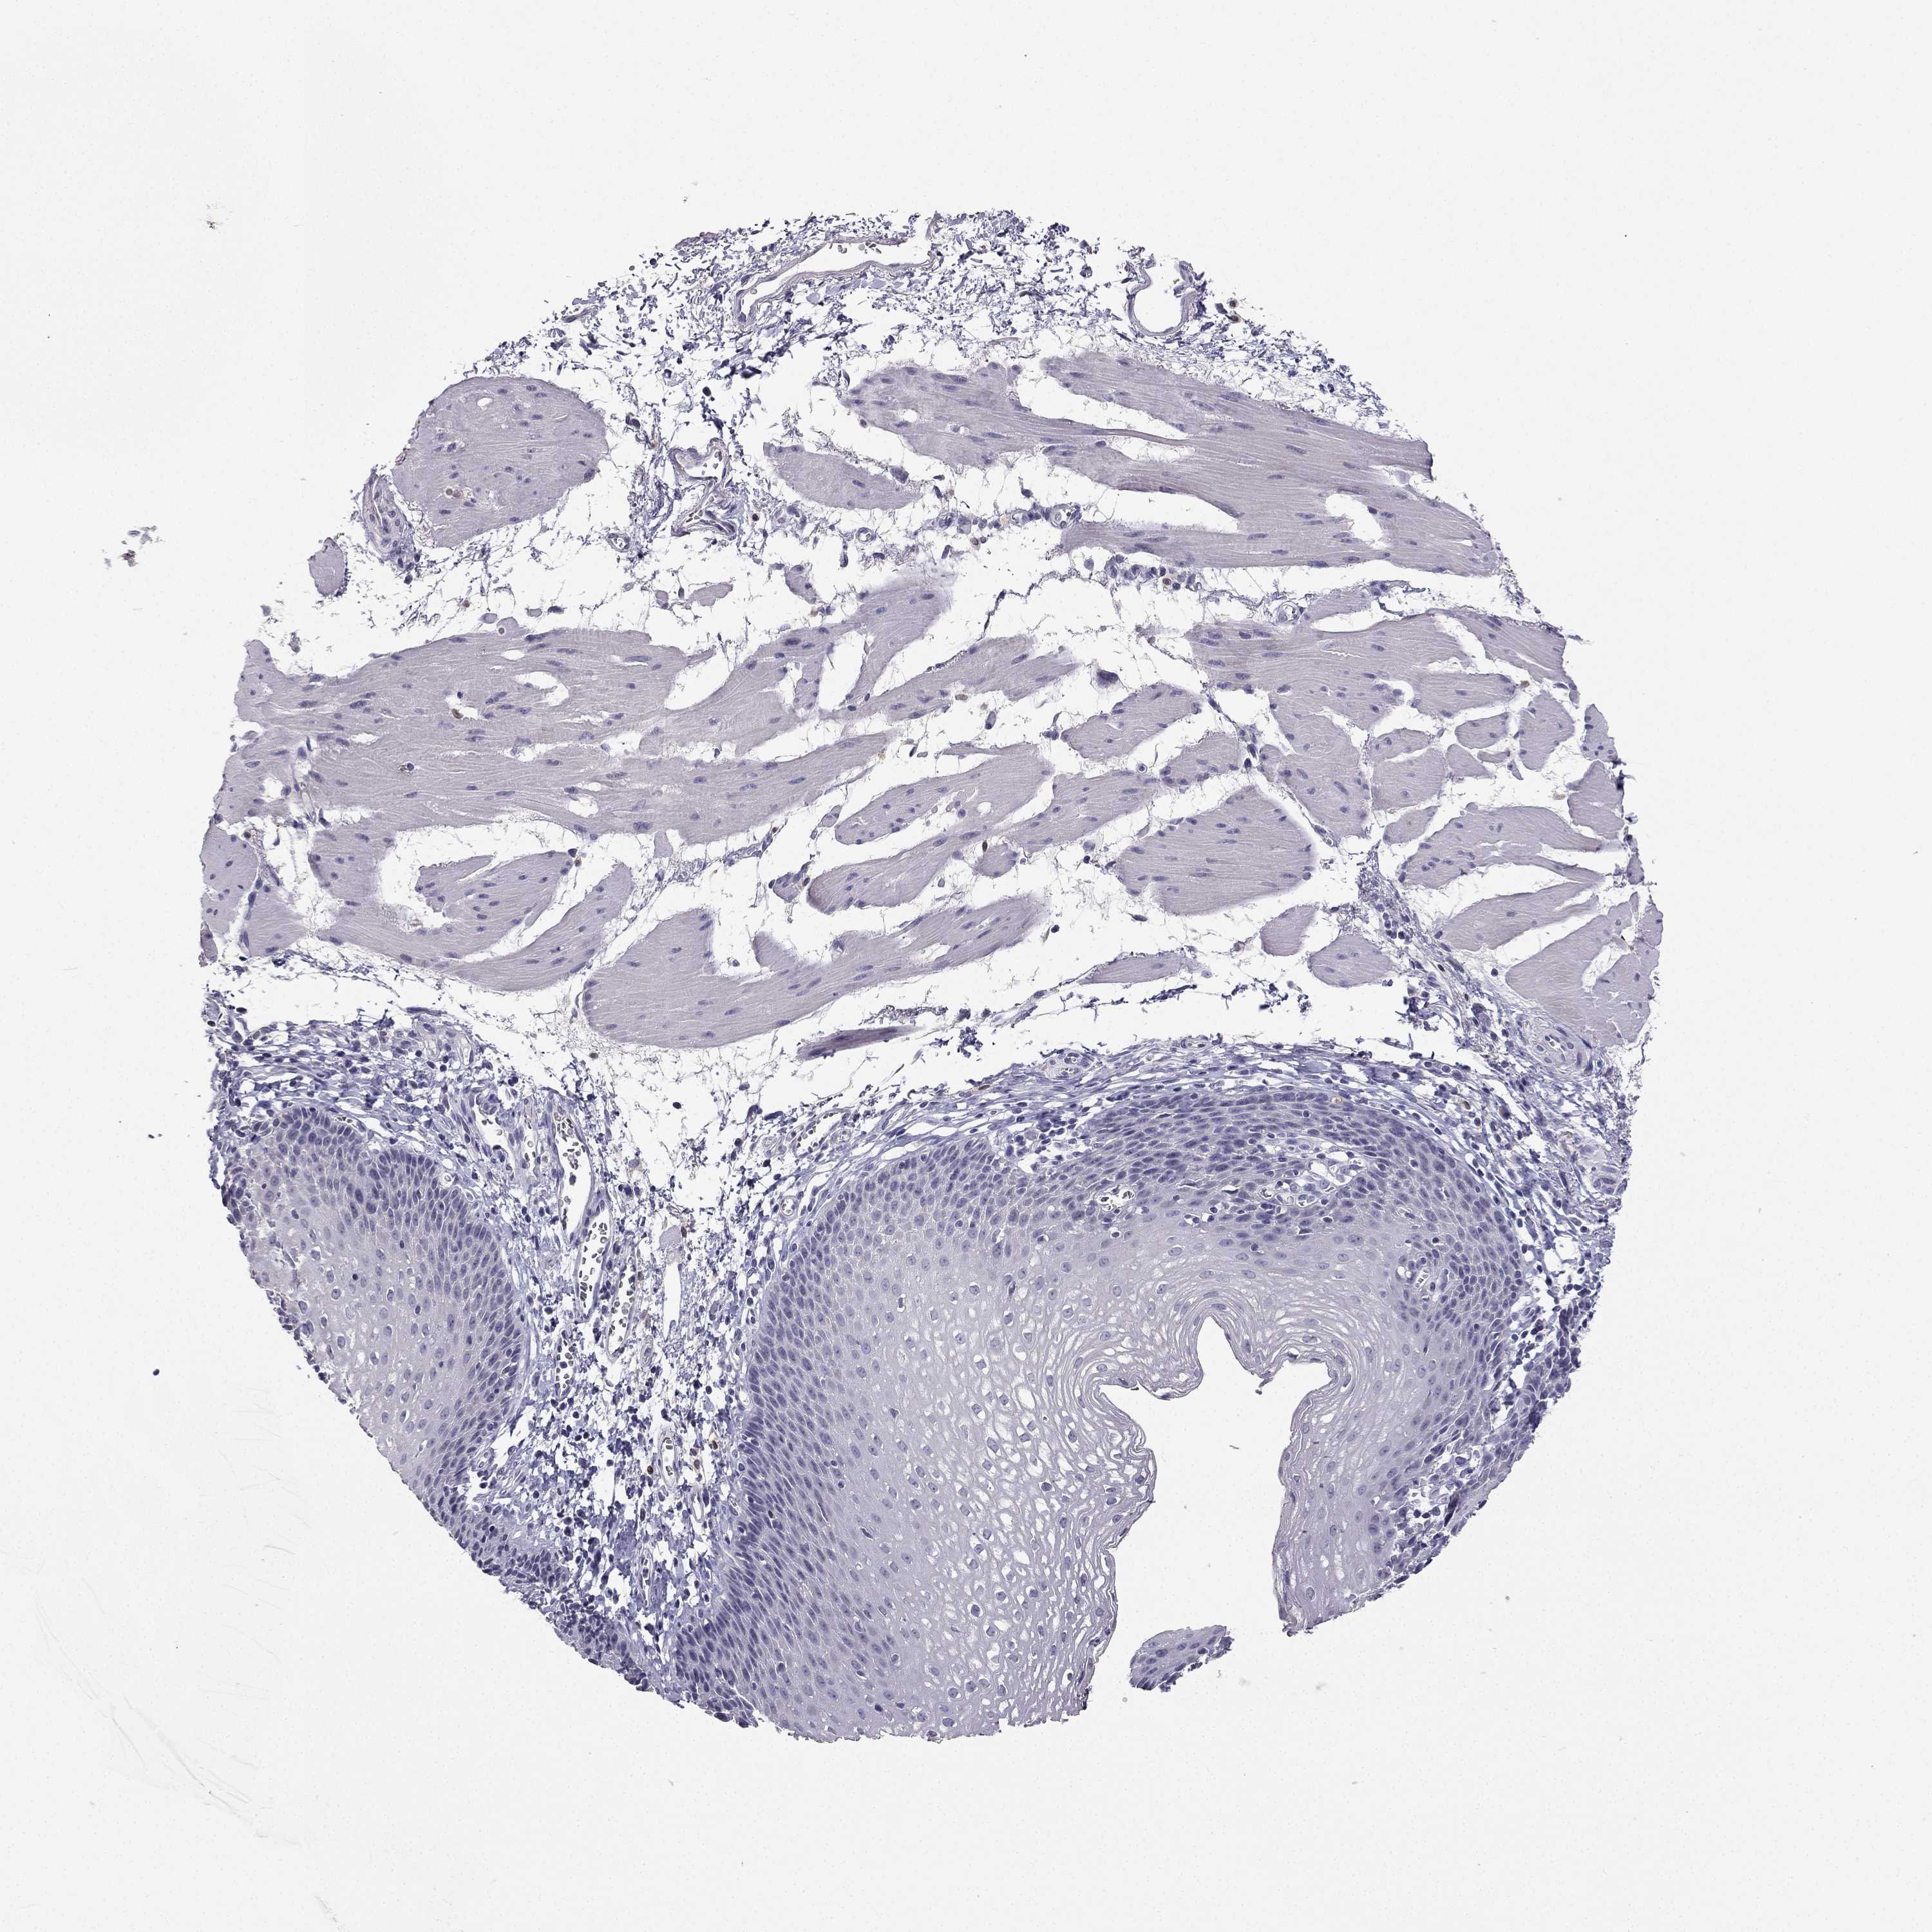

ESOPHAGUS - Antibody stainingi

Antibody staining in the annotated cell types in the current human tissue is reported as not detected, low, medium, or high, based on conventional immunohistochemistry profiling in selected tissues. This score is based on the combination of the staining intensity and fraction of stained cells.

Each image is clickable and will lead to virtual microscopy that enables deeper exploration of all samples and also displays staining intensity scores, fraction scores and subcellular localization as well as patient and tissue information for each sample.

Antibody HPA007305Antibody HPA007306Antibody CAB000106

Squamous epithelial cells Not detectedLowNot detected